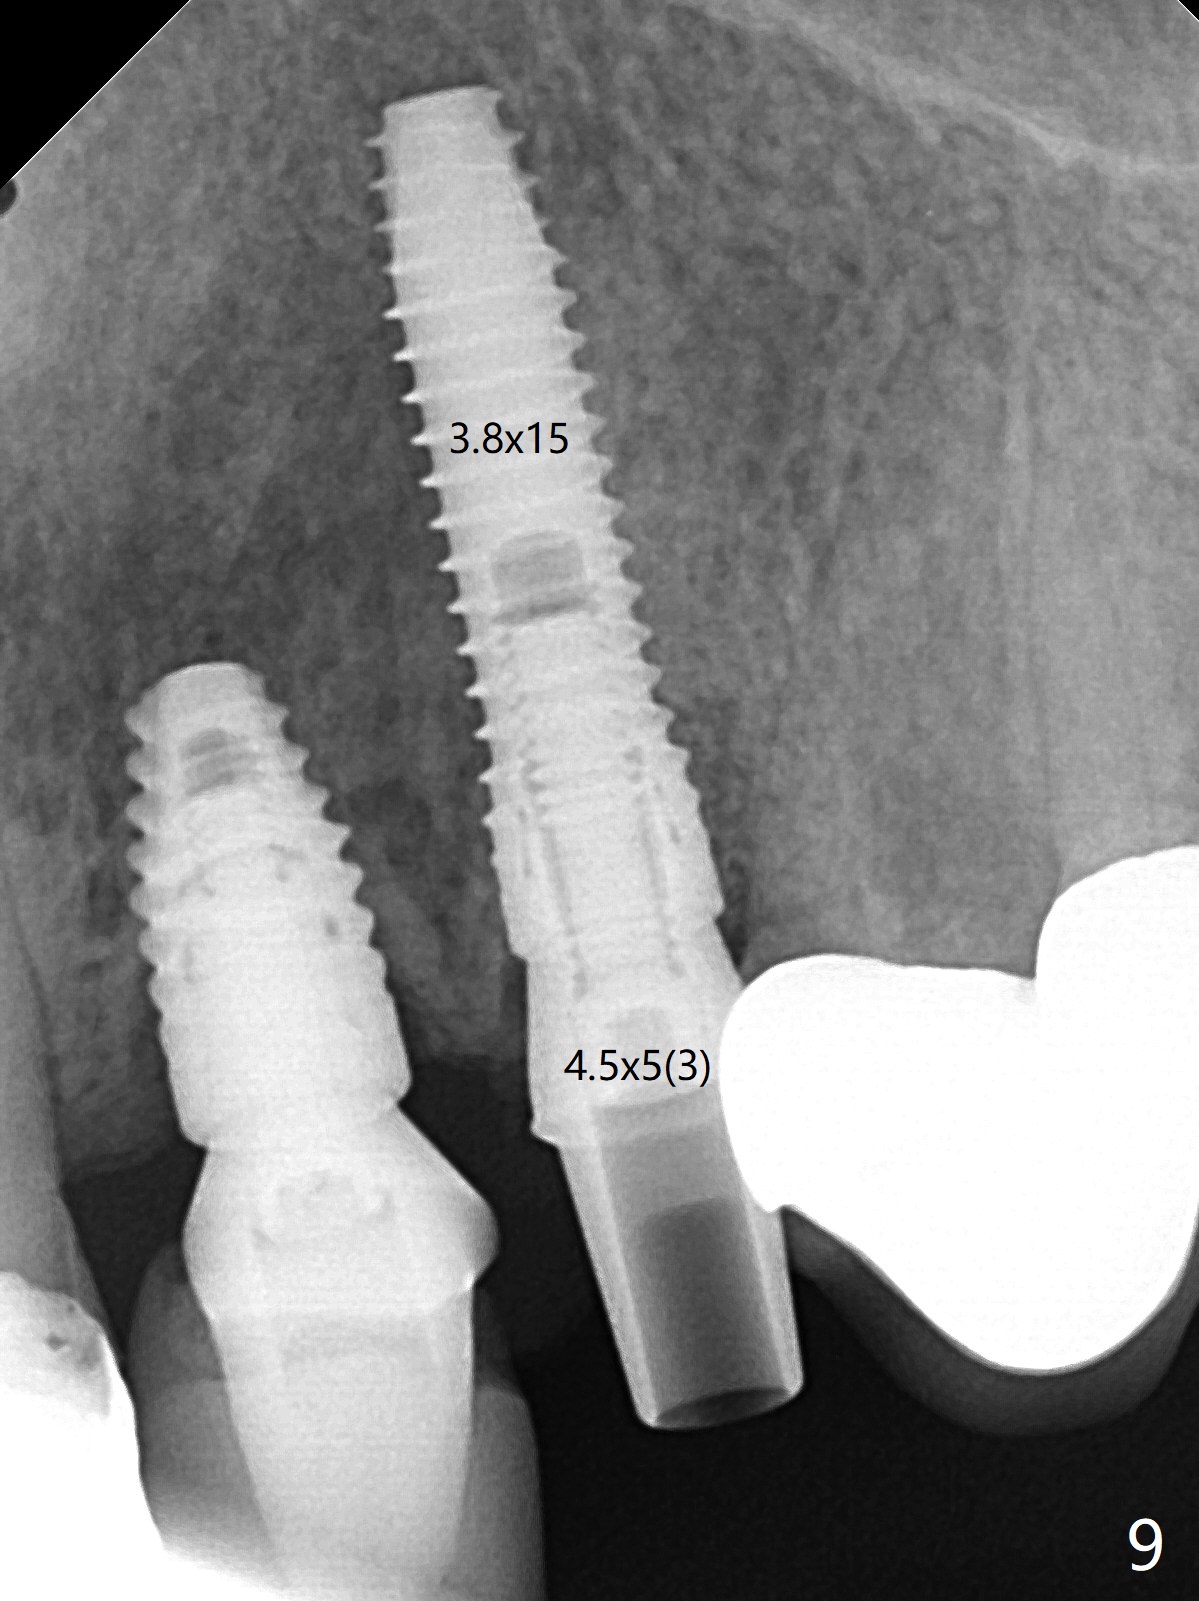

左上尖牙拔除前发现远中腭侧瘘道,拔除后发现相对牙槽嵴骨缺损(图一(术前CT):*),其实患牙根尖在颊侧骨板颊侧(图二:>),拔除后,根尖骨板缺损(图三:>),由于后者离颊侧牙槽嵴(图四:红箭头)远,骨粉修复重要性不如腭侧牙槽嵴(图四:白箭头),当窄植体植入后(图四:绿色),首先在腭侧植骨(图五:红圆圈),因为基台放置后(图六:粉红色),腭侧植骨开口狭窄(图六:白箭头)。即刻种植总是腭侧,颊侧间隙大,颊侧根尖缺损填骨应该容易(图七:橘黄色圆圈),即使不全(*),无关大局。徒手初步钻洞(图八),种植(图九)方向尚可,植骨好像完全(图十:*)。术后一周临时牙冠(11,尖牙)比侧切牙还短(图十一),随着愈合,尖牙牙冠会比双尖牙还短,因为植体偏腭侧,可能需要调整临时牙冠边缘。颊侧牙龈单纯疱疹感染,颊侧根尖仍有疼痛,腭侧瘘道缩小。